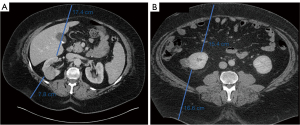

The final cohort included 22 patients with a median BMI of 44.9 kg/m2 [interquartile range (IQR), 42.1–48.8] and median age of 61.0 years (IQR, 47.9–64.6 years). Median duration of follow up was 52 months. Patient demographics and preoperative clinical information are summarized in Table 1. Half (n=11) of the patients were male, and the median preoperative estimated glomerular filtration rate was 81.2 mL/min. The majority (55%) of tumors had a low RENAL (radius, exophytic/endophytic, nearness, anterior/posterior, location) nephrometry score (Table 2). Expectedly, the tumors were predominantly located posteriorly (86.4%). Representative preoperative images of tumors in a male and female patient can be seen in Figure 2. Five patients underwent a renal mass biopsy before undergoing surgery, and the pathologic results were clear-cell RCC in two, papillary RCC in two, and non-diagnostic in one.